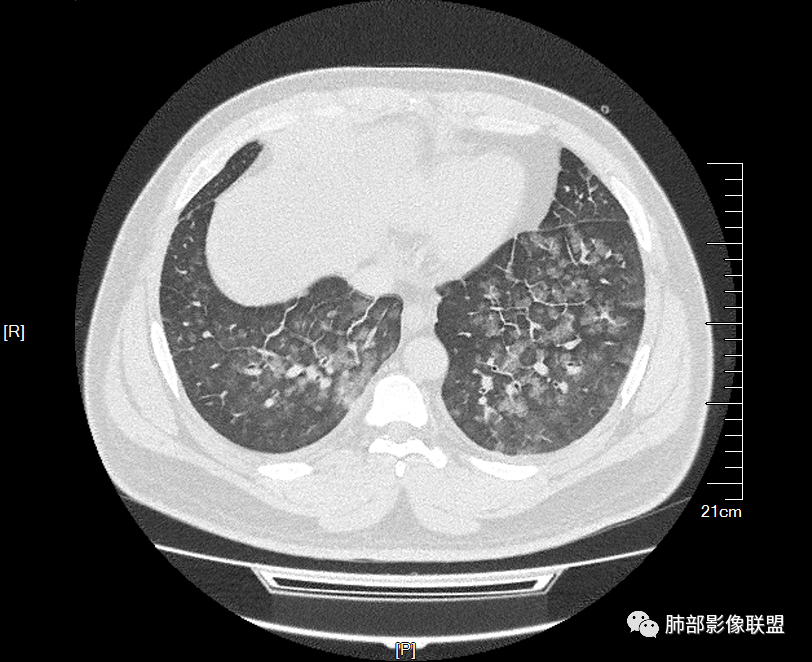

双肺多发弥漫性磨玻璃结节影,大小不一,形态不规则,部分融合,支气管未见明显扩张,部分血管束略增粗,叶裂胸膜增厚,临床有痛风,左足痛6天,考虑:1:痛风结节(一般实性结节,很少磨玻璃结节影)2:血管炎?3:病毒性肺炎(水痘-疱疹肺炎?)

双肺多发腺泡结节及磨玻璃,小叶间隔增厚(大网格状),腺泡结节内及磨玻璃内可见细网格影(小叶内间隔增厚),影像表现符合肺泡出血改变,血肌酐升高,考虑肺肾综合征。鉴别肺水肿。

年轻男性,既往血肌酐升高,左足痛六天入院,有痛风及高血压病史。CT示双肺多发磨玻璃结节影,不规则,部分融合成团或片状,小叶间隔增厚,以双下肺为明显,叶间胸膜亦见增厚。考虑为1.Good-Pasture综合征。2.病毒性肺炎?3.肺水肿?

年轻男性,痛风史,高血压史,肌酐高,左足痛6天入院。胸CT:双肺多发弥漫性磨玻璃结节影,大小不一,部分融合,上中下肺都有,中内带多,胸膜下少。部分血管束略增粗,小叶内间隔、小叶间隔增厚,下肺明显,左室大。叶裂胸膜增厚。临床有痛风,左足痛6天,考虑:心衰、间质性肺水肿?弥漫性肺泡出血?鉴别:MPA,肺肾综合征,痛风结节等。

多发GGO结节,边界清,以全小叶、小叶中心为主:

GGO背景

小叶间隔增厚,无明显重力趋势

少量积液,脂肪肝

这里有一点重力趋势

中轴间质稍增厚

细网格也明显

中轴间质增厚,小叶间隔增厚,小叶内间质增厚,部分重力作用,双侧对称,胸水,按理淋巴道回流受阻有

肺水肿类病变有

问题是腺泡结节如何解释?